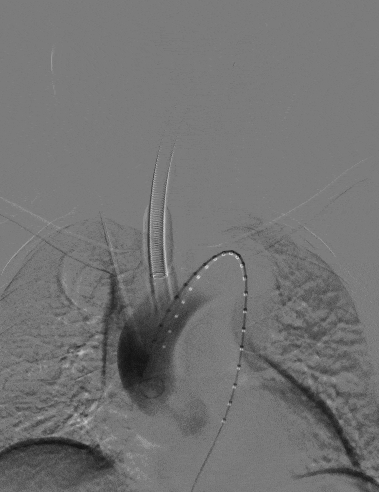

1、患者平躺后行全身麻醉手术,穿刺患者左肱动脉与右股动脉,并在左肱动脉置入穿刺鞘后,从右股动脉导入一根长鞘,长鞘里同走超硬导丝与软泥鳅导丝,自下而上地探索真腔,在软泥鳅导丝穿出左肱动脉后,完成左肱动脉-右股动脉的导丝通路建立后,从左肱动脉导入导引导管,接着在右股动脉交换泥鳅导丝为分支导丝,完成分支导丝通路建立,然后从右股动脉长鞘内并行导入造影导管至升主动脉,进行术前造影,确认患者为B型主动脉夹层。

长鞘走双导丝,泥鳅超选LSA

动脉长鞘怎么置入宁波市第二医院血管外科运用Castor®单分支支架结合长鞘建立导丝通路的方法治疗Stanford B型胸主动脉夹层一例_https://www.jmylbn.com_新闻资讯_第7张

术前DSA造影